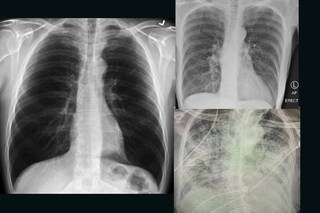

സാധാരണ ആരോഗ്യമുള്ള ഒരാളുടെ ശ്വാസകോശവും ഒരു പുകവലിക്കുന്ന ആളുടെ ശ്വാസകോശവും കോവിഡ് ബാധിച്ച ഒരാളുടെ ശ്വാസകോശവുമാണ് ഇവർ പങ്കുവച്ചത്. സാധാരണ ശ്വാസകോശം ഇരുണ്ടതും കാണാവുന്നതുമാണ്.

പുകവലിക്കുന്ന ആളുടെ ശ്വാസകോശം

പുകവലിക്കുന്ന ആളുടെ ശ്വാസകോശം ഭാഗികമായി വെളുത്തതാണ്. എന്നാൽ, കൊറോണ വൈറസ് രോഗിയുടെ ശ്വാസകോശം കാണാൻ കഴിയാത്ത വിധത്തിലുള്ളതാണ്.

കോവിഡ് ബാധിച്ചതിനു ശേഷമുള്ള ശ്വാസകോശം

ട്വിറ്ററിലാണ് അദ്ദേഹം ഇക്കാര്യം പങ്കുവച്ചത്. കോവിഡ് ബാധിച്ചതിനു ശേഷമുള്ള ശ്വാസകോശം നല്ലൊരു പുകവലിക്കാരന്റെ ശ്വാസകോശത്തേക്കാൾ മോശമാണെന്നും അദ്ദേഹം കുറിക്കുന്നു. ശ്വാസതടസം ഉൾപ്പെടെയുള്ള അസ്വസ്ഥതകൾക്ക് അത് കാരണമാകുന്നു.